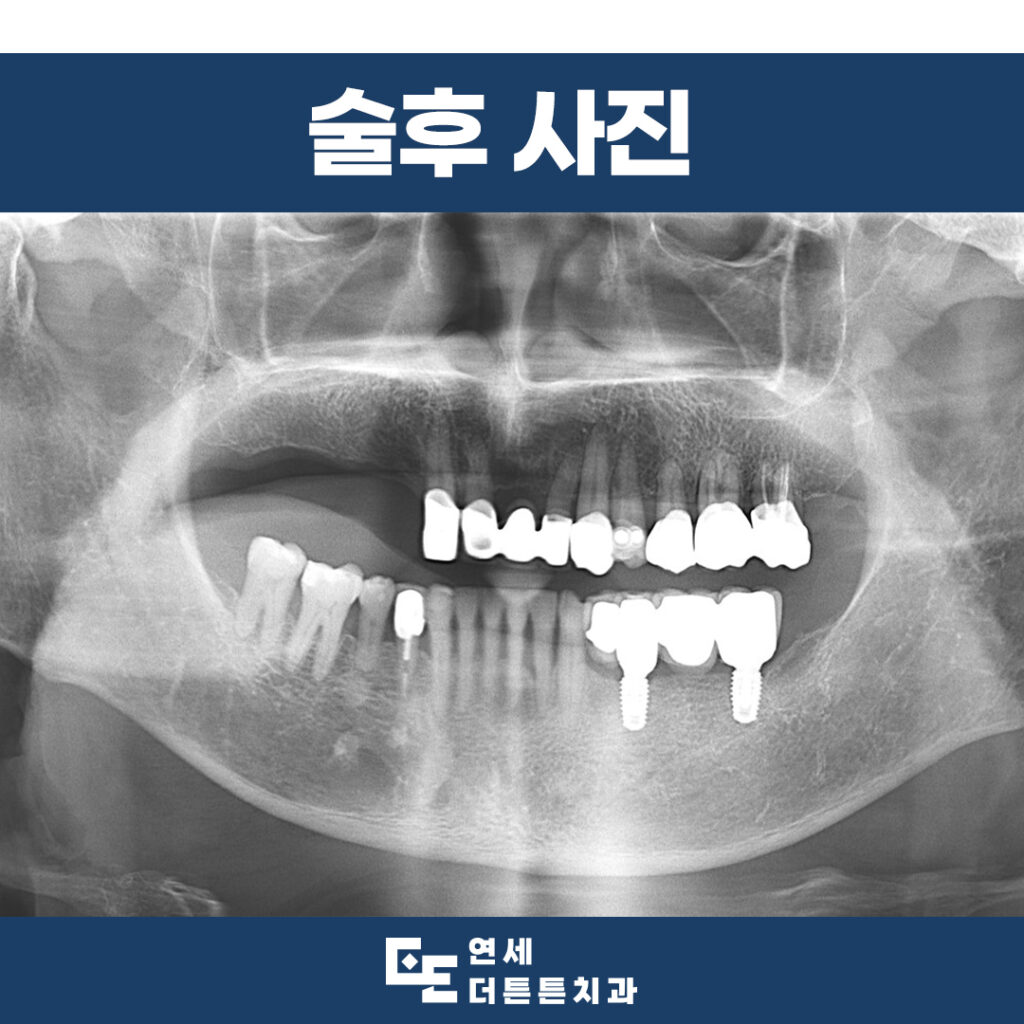

따라서 아래쪽은 보험 임플란트를

이용하여 무치악 부위를 수복하기로 하였고

위쪽은 크라운을 이용하여 후방을 연장한

틀니를 사용할 수 있도록 계획하였습니다.

약 6개월의 기간 동안 임시틀니를

사용하시도록 하여 수직 고경을 안정화시키고

심미성을 개선할 수 있도록 한 뒤

최종 모든 치료를 마무리하였습니다.

6개월의 기간 동안 임시 수복물을 통해

앞니가 앞으로 나올 수 있게 유도하여

최종 수복물에 반영할 수 있도록 하였습니다.

최종적으로 금속 도재관을 이용한

위, 아래 보철물 및 편측의 후방 연장

틀니까지 문제없이 마무리하였습니다.

치료 전, 구강 내 엇갈린 교합으로 인해

틀니의 유지 안정성이 떨어질 것을 예상하였지만

치료 과정에서 임시틀니와 임시 보철물을 통해

수직 고경 안정화를 진행하여 최종 보철물에 반영하였으므로

어금니 부위 지지를 확보하여

앞니의 배열 관계까지 정상화시킬 수 있었습니다.